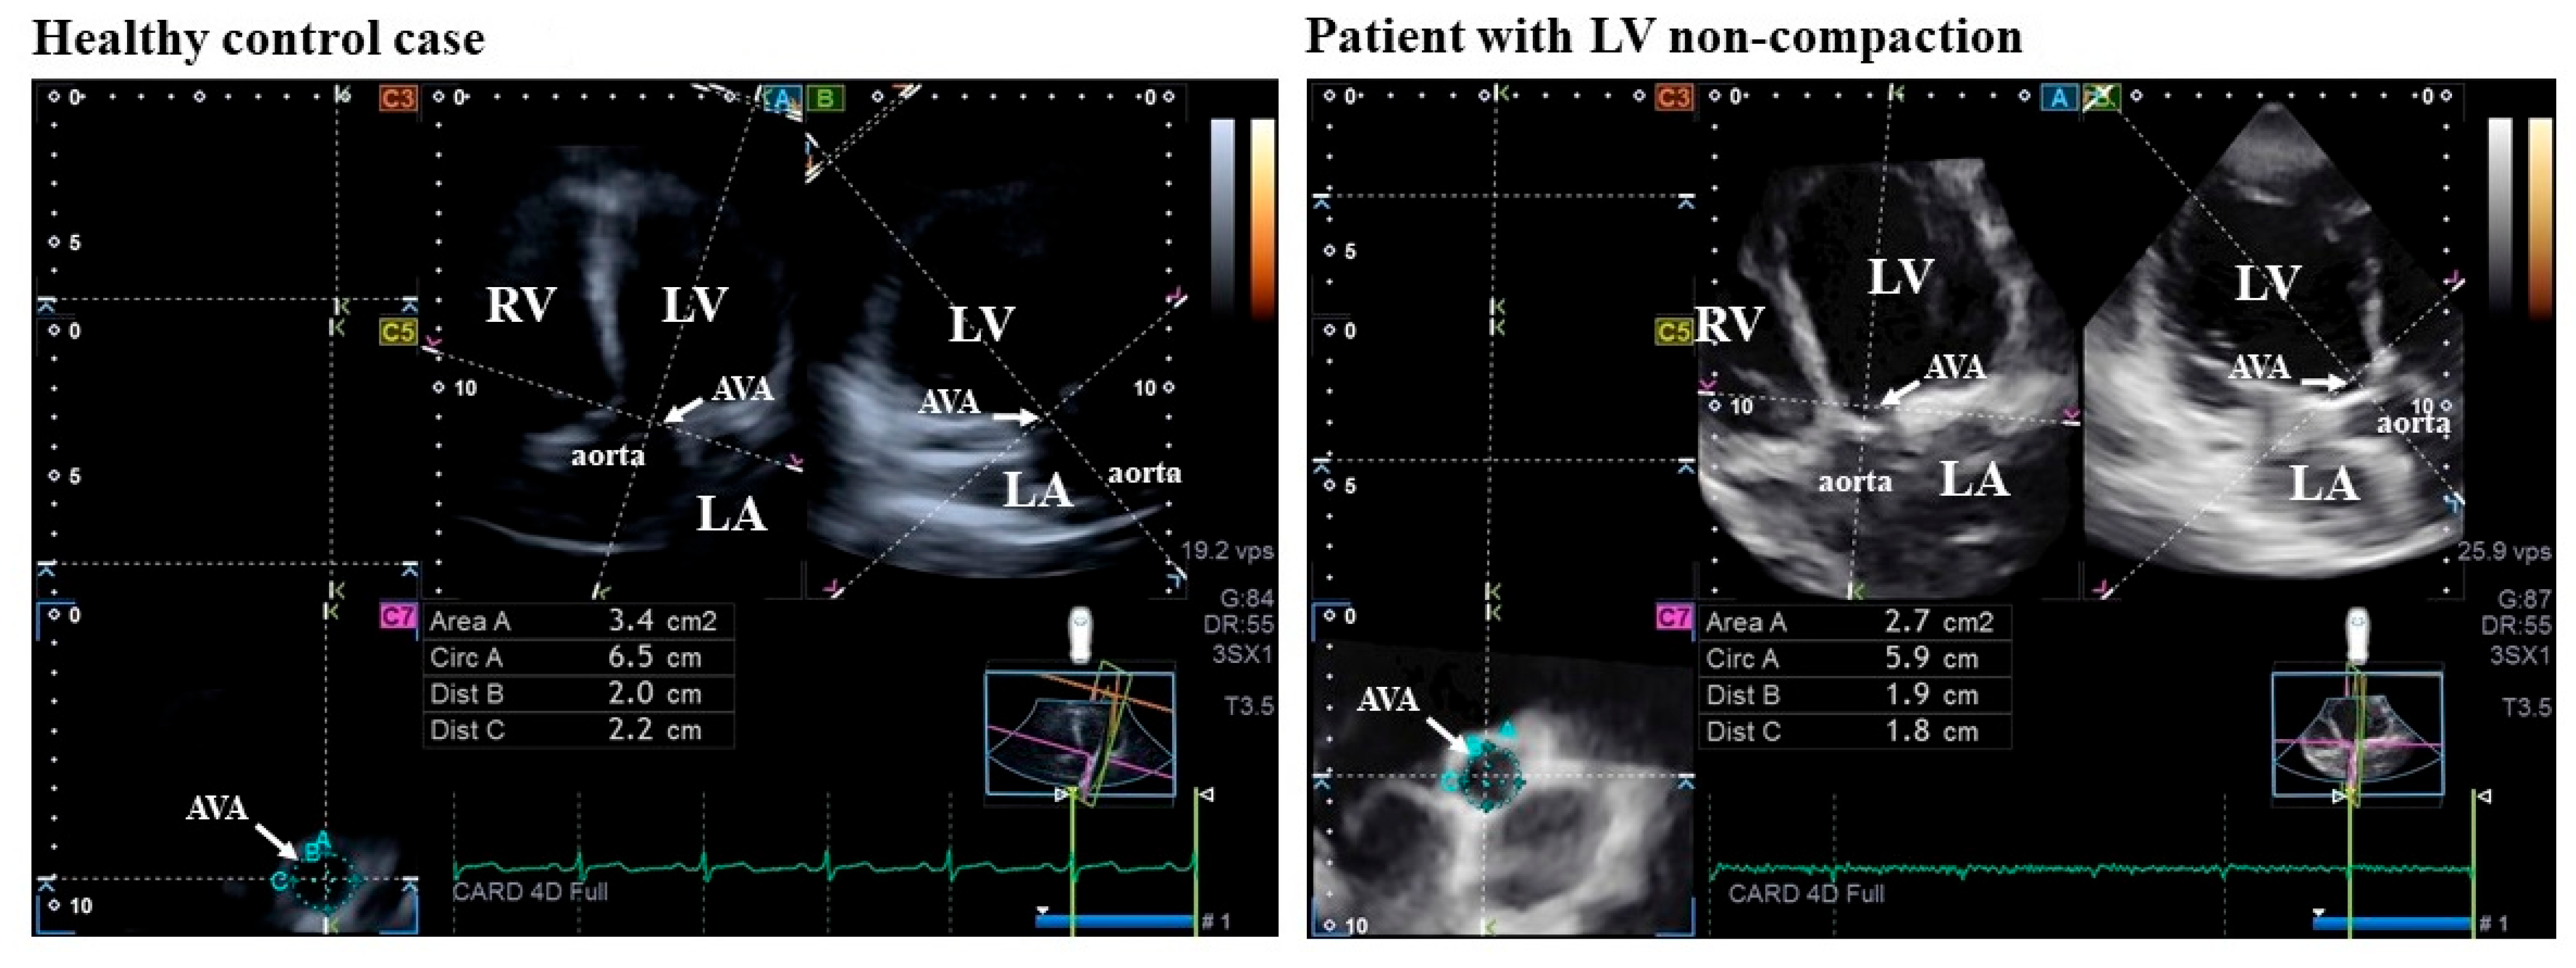

| AVA-Dmax-D (cm) | 2.08 ± 0.26 | 2.18 ± 0.28 * # | 1.99 ± 0.20 * | 2.04 ± 0.48 | 2.08 ± 0.50 * | 1.93 ± 0.37 |

| AVA-Dmin-D (cm) | 1.86 ± 0.26 | 1.94 ± 0.23 ‡ | 1.79 ± 0.27 * | 1.72 ± 0.27 * | 1.70 ± 0.29 * | 1.77 ± 0.21 |

| AVA-A-D (cm2) | 3.30 ± 0.78 | 3.55 ± 0.82 * # | 3.09 ± 0.67 * | 3.19 ± 1.08 | 3.26 ± 1.13 * | 3.00 ± 0.88 |

| AVA-P-D (cm) | 6.48 ± 0.78 | 6.74 ± 0.79 * # | 6.26 ± 0.70 * | 6.33 ± 1.13 | 6.40 ± 1.20 * | 6.13 ± 0.87 |

| AVA-Dmax-S (cm) | 2.02 ± 0.27 | 1.97 ± 0.28 | 2.06 ± 0.26 | 1.92 ± 0.50 | 1.81 ± 0.53 | 2.20 ± 0.22 |

| AVA-Dmin-S (cm) | 1.90 ± 0.29 † | 1.86 ± 0.34 ‡ | 1.93 ± 0.24 | 1.58 ± 0.40 | 1.49 ± 0.39 | 1.83 ± 0.31 |

| AVA-A-S (cm2) | 3.33 ± 0.85 † | 3.07 ± 0.93 | 3.55 ± 0.71 | 2.69 ± 1.04 | 2.37 ± 0.89 | 3.67 ± 0.82 |

| AVA-P-S (cm) | 6.48 ± 0.88 | 6.23 ± 0.94 | 6.69 ± 0.77 | 6.02 ± 1.31 | 5.76 ± 1.38 | 6.80 ± 0.70 |

| AAPSE (cm) | 1.12 ± 0.24 † | 1.11 ± 0.21 ‡ | 1.12 ± 0.27 | 0.78 ± 0.28 | 0.72 ± 0.21 | 0.97 ± 0.37 |